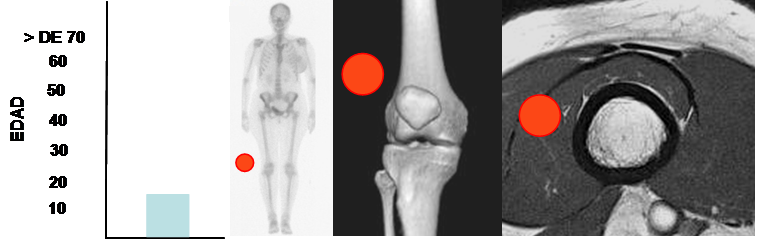

Fig 144. Hemangioma de tejidos blandos.

Mayor frecuencia en niños. Predominio en tejidos superficiales.